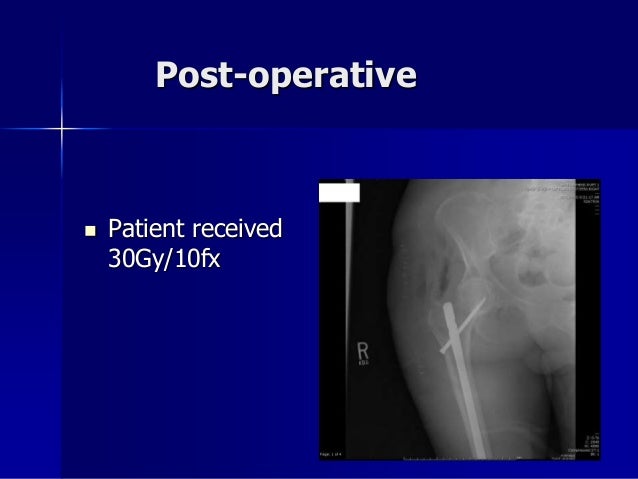

1. 1. Ακτινοθεραπεία Ξ. Βακάλης Ακτινοθεραπευτής Ογκολόγος Ιατρικού κέντρου Αθηνών

2. 2. Disclosures  None